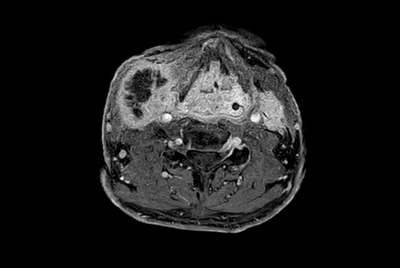

SmartSpeed Traumatic Knee imaging